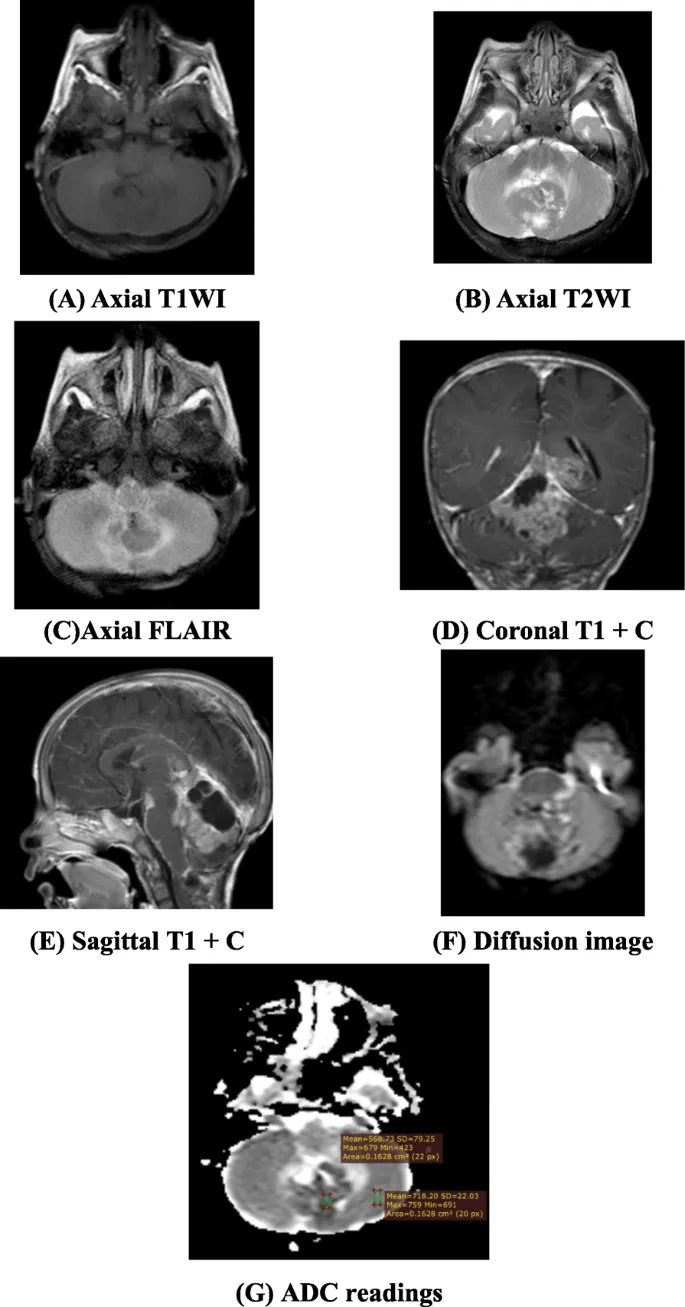

- CNS Tumors (Posterior Fossa commonest): 📌 My Apple Eats Bugs (Medulloblastoma, Astrocytoma, Ependymoma, Brainstem glioma).

- Medulloblastoma: Midline (vermis), hyperdense (CT), ↓ADC, hydrocephalus.

⭐ Medulloblastoma: Most common malignant pediatric brain tumor; often shows "Zuckerguss" (drop metastases) on spinal MRI.

- Ependymoma: 4th ventricle, "plastic" (through foramina Luschka/Magendie), calcification.